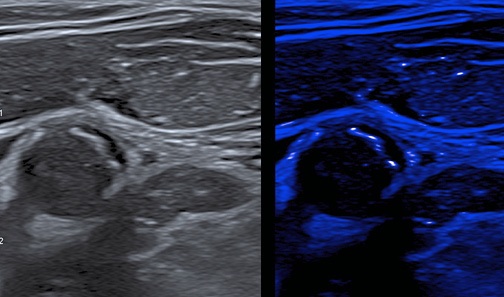

Рис. 5. Ультразвуковое изображение АСБ с множественными МК в покрышке в режиме MicroPure.

Примечание: цветное изображение доступно в электронной версии журнала.